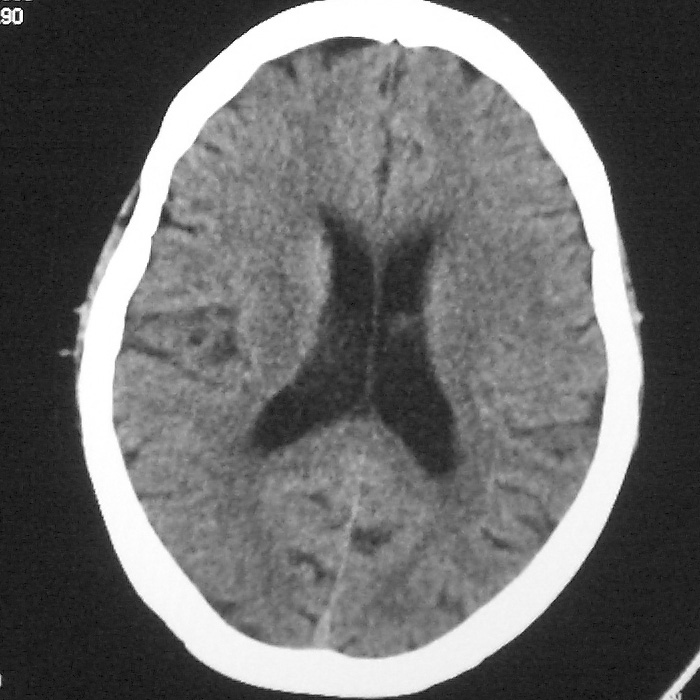

f,70y,口角歪斜、流涎、吐词不清三天

左侧大脑基底节区点状低密度影,边缘清楚,左侧腔梗或软化灶,没什么问题啊?

症状这么明显的话一般不会是单纯面神经麻痹引起的,最好做个mri,如果确实没有问题的话才能考虑面神经麻痹,毕竟这两种病的治疗和预后不一样,这个病人还有脑白质疏松。

左侧半卵圆中心腔梗应当比较明确,右侧基底节好象不明显,不好说,做个mri明确吧

双侧多发腔梗

右侧基底,左侧半卵圆中心腔梗

1、右侧基底,左侧半卵圆中心腔梗。2脑萎缩。

左侧腔隙性梗塞灶,脑萎缩。

左侧基底节区示点状低密度灶,边界清楚,密度均匀,余所示无著变。

意见:腔隙性脑梗塞(左基底节区)

各位老师,报告这么写可以吗?右侧我没有看出来。

左侧半卵圆中心,右侧基底节腔梗。再加个脑萎缩吧

双侧多发腔梗 脑萎缩